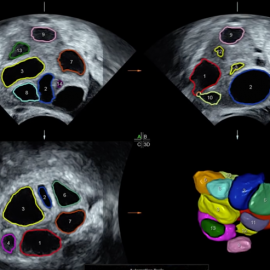

يقصد به تحفيز المبايض لتكوين عدد كافي ونوعية جيدة من البويضات، ويتم ذلك بإعطاء حقن هرمونية خاصة ضمن برامج متعددة وتوفير الضبط اللازم للهرمونات (منع حدوث الإباضة مبكرة) مع المراقبة المستمرة بالإيكو المهبلي.

- يجب مراقبة النساء اللواتي يستخدمن هذا الدواء مخبرياً وبالأمواج فوق الصوتية لتقليل خطر حدوث فرط استجابة المبيض والحمل المتعدد وذلك لأنه أشد تحريضاً للإباضة من الأدوية الفموية .

تعتبر كل حالة سواء كانت جماع مؤقت أو حقن داخل الرحم أو إخصاب خارج الجسم مستقلة ويجب أن تراقب بشدة بتحليل مستوى الاستروجين وبالأمواج فوق الصوتية لتقليل احتمال الخطر ولتحديد زمن الإباضة بدقة .

هو حقن تحت الجلد تحرض مبدئياً ثم تثبط الإفراز الدماغي ل LH , FSH وتستخدم في الإخصاب المساعد خارج الجسم لتحسين عدد الجريبات وذلك بمنع الجريب الكبير من التطور .